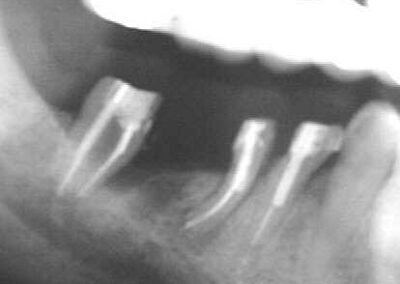

Das nebenstehende Bild zeigt einen solchen von der distalen Wurzel des Zahnes 46 ausgehenden kombinierten Endodontitis – Parodontitis-Fall aus August 1999.

Der Zahn 48 konnte aufgrund einer bestehenden via falsa nicht erhalten werden.

Hier sieht man den gleichen Fall fast ein Jahr später nach Hemisektion von 46, Ausheilung der Entzündung nach sorgfältiger Desinfektion und anschließender Wurzelfüllung, Versorgung mit Radix-Ankern und Kunststoff-Aufbauten in SÄT und Langzeit-Provisorien kurz vor Eingliederung der endgültigen Brücke.

Man beachte den „wundersamen Knochengewinn“ durch Elimination der Entzündung mesial 47.

Ein herausnehmbarer Zahnersatz oder Implantate konnten so vermieden werden.